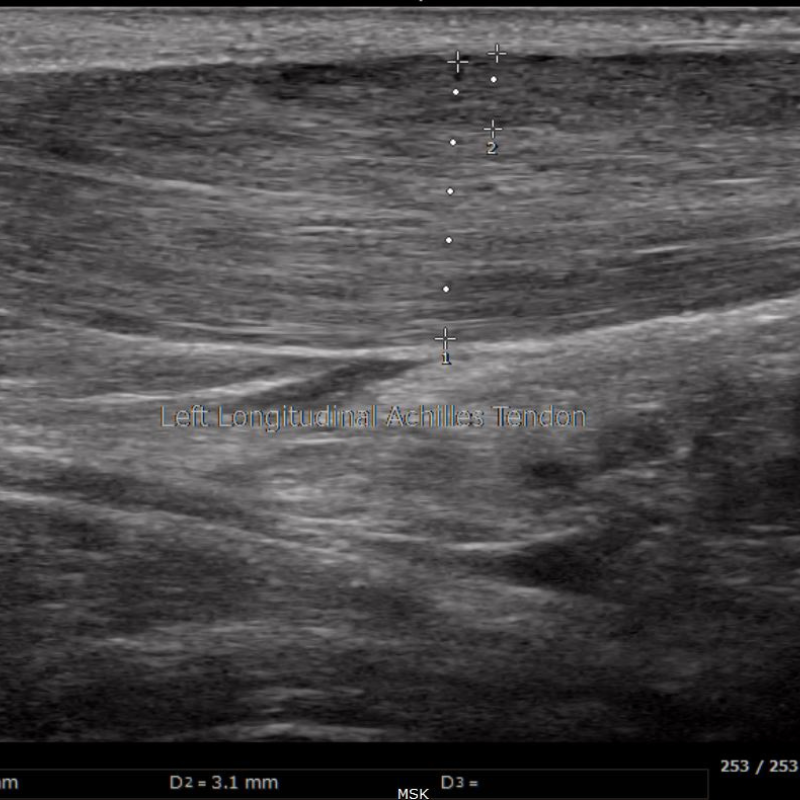

Diagnostic ultrasound works much like the device used during pregnancy to capture images of a baby in the womb. In podiatry, we use this safe, non-invasive tool to see tendons, ligaments, joints, and even bone in real time. Unlike X-rays or MRIs, ultrasound allows our podiatrists to gently move and stress your joints during the scan, giving a more complete understanding of what’s causing your pain.

• Tendonities or Tendon injuries (Achilles, peroneal, posterior tibial)

Scanning: The podiatrist moves a handheld device over the area, sending sound waves through the tissues. It takes about 45 minutes or more, depending on the area being scanned.

Image created: Returning echoes form a live image on the screen.

Review: Images are interpreted on the spot by our board-certified podiatrists.